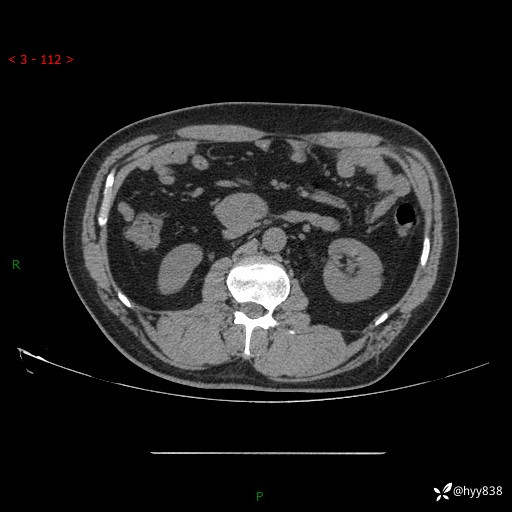

腹部CT平扫